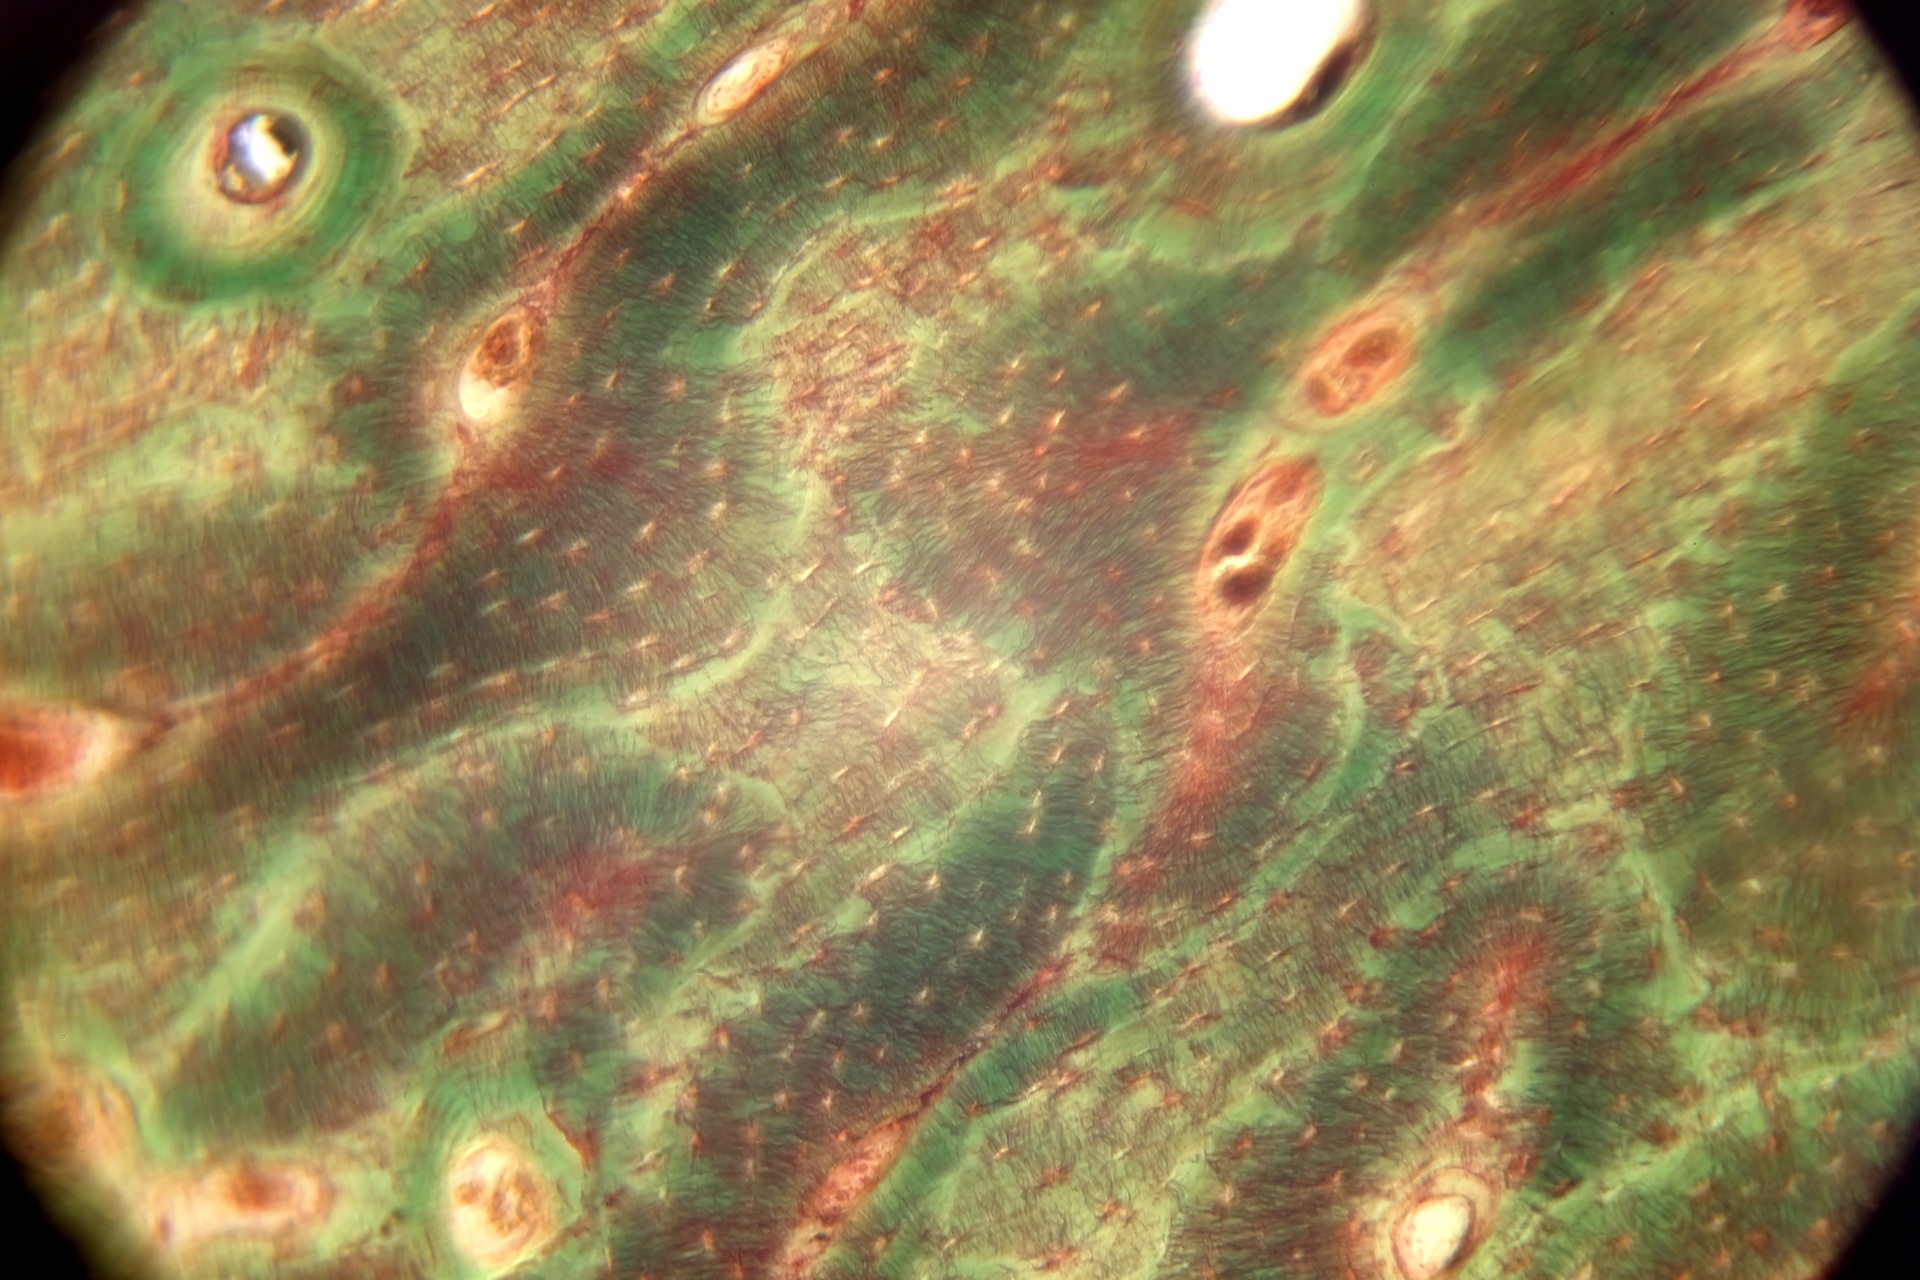

Берцовая кость человека